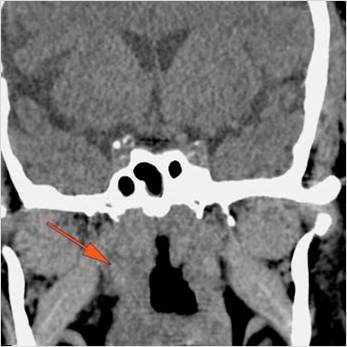

There is evidence of thrombus, thrombophlebitis or other occlusive or inflammatory process of the cavernous sinus. [Yes/No]

Findings are consistent with the clinical diagnosis of acute or subacute sinusitis complicated by orbital venous, cavernous sinus or other venous or dural sinus thrombosis.